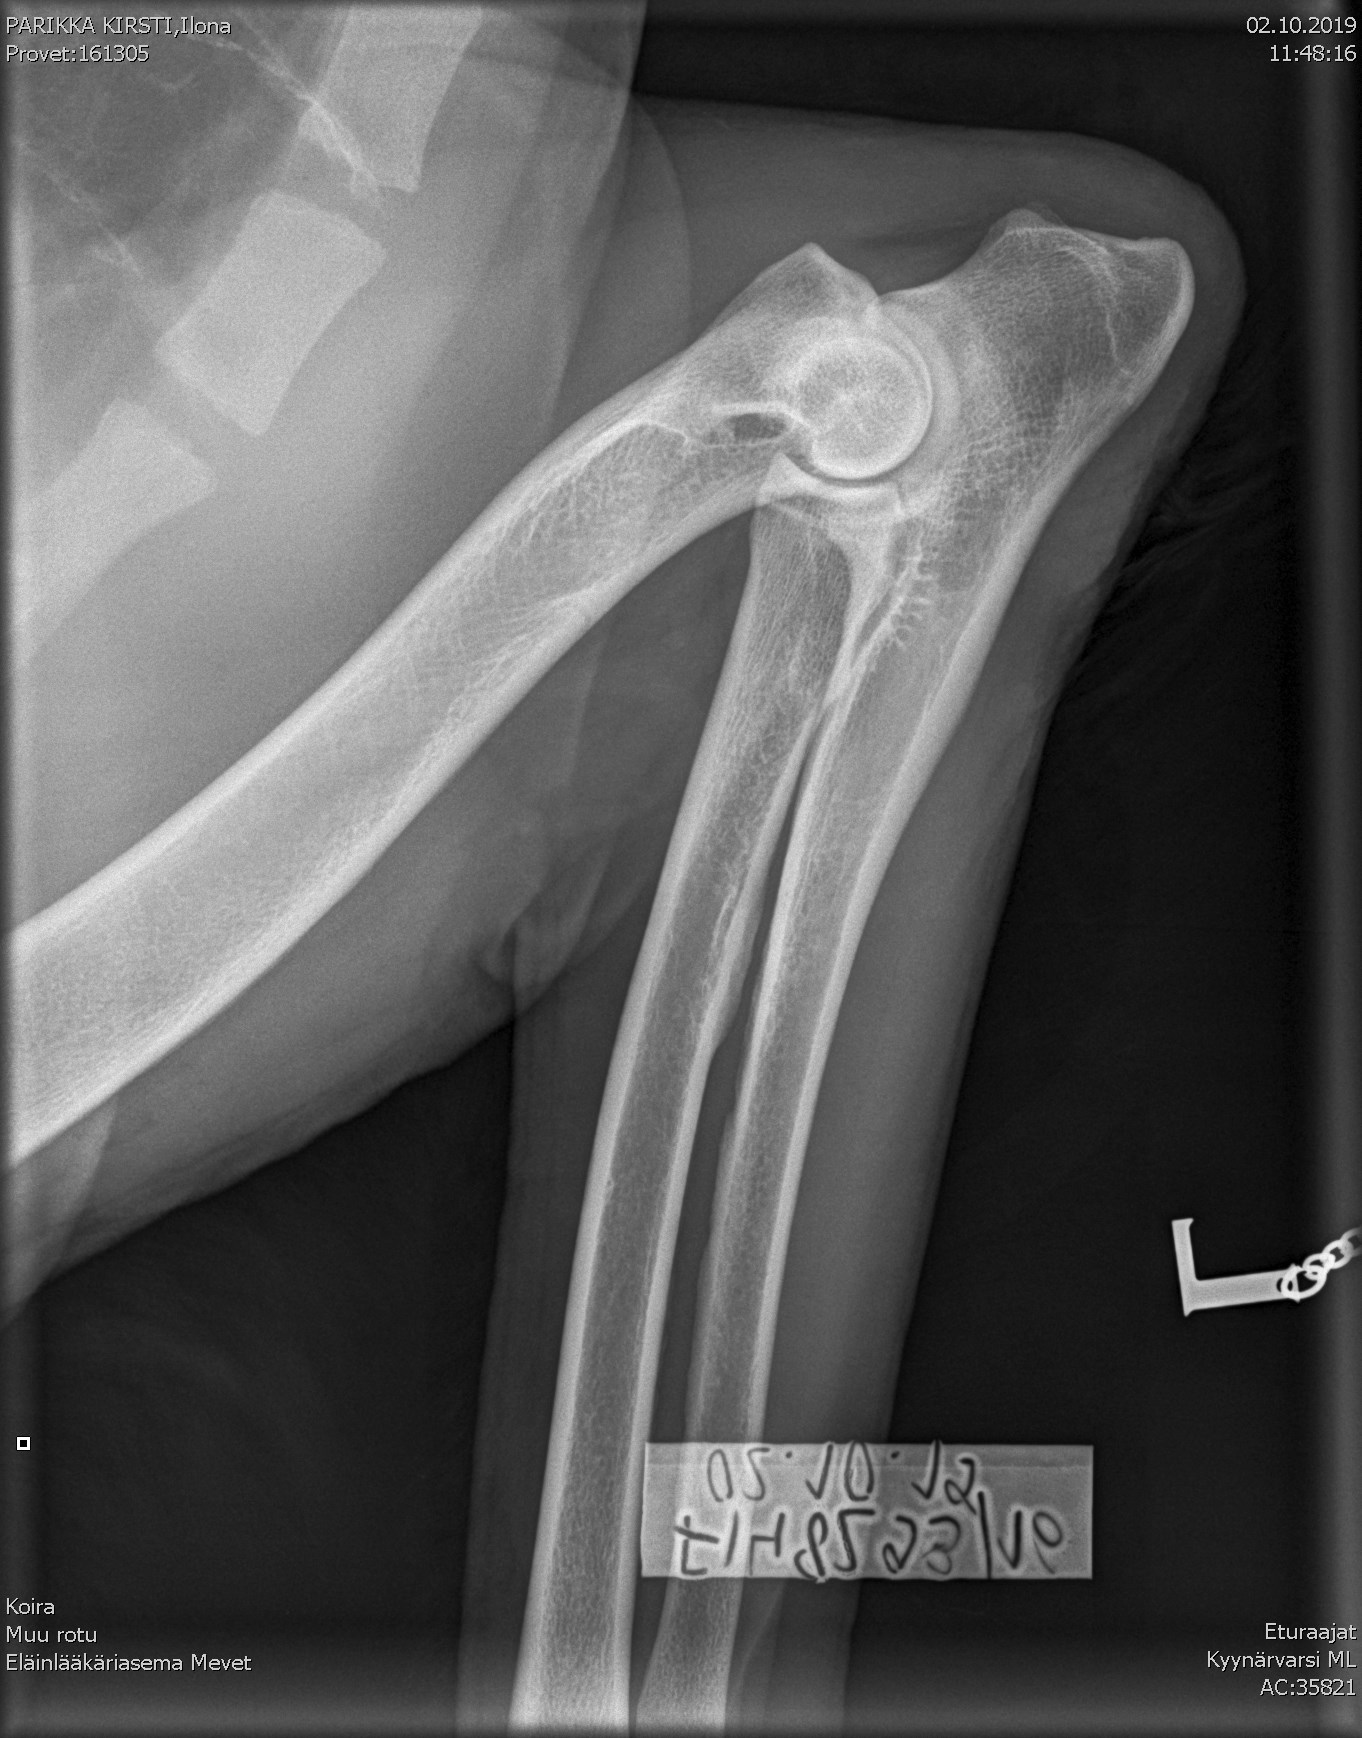

Ilona's elbow X-ray